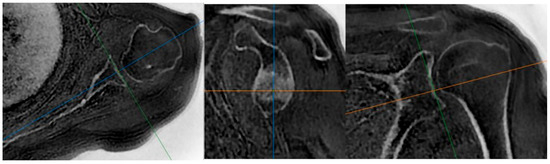

ZTE MRI for Rotator Cuff Tear Arthropathy: Integrated Bone–Muscle Analysis and Its Association with Pseudoparesis

by Engin Türkay Yılmaz, Serkan İbik, Vedat Yaman, Şeyda Betül Fındık, Üstün Aydıngöz and Gazi Huri

J. Clin. Med. 2025, 14(23), 8597; https://doi.org/10.3390/jcm14238597 - 4 Dec 2025

Background/Objectives: Evaluating glenoid changes in rotator cuff tear arthropathy (RCTA) is crucial for preoperative planning. MRI with zero echo time (ZTE) sequence, which produces CT-like images, allows for the assessment of osseous morphology as well as factors contributing to pseudoparesis in RCTA patients. [...] Read more.

Background/Objectives: Evaluating glenoid changes in rotator cuff tear arthropathy (RCTA) is crucial for preoperative planning. MRI with zero echo time (ZTE) sequence, which produces CT-like images, allows for the assessment of osseous morphology as well as factors contributing to pseudoparesis in RCTA patients. Methods: In this retrospective study, using 3T MRI, glenoid version, glenoid vault depth, humeral subluxation index, humeral head medialization, critical shoulder angle, glenoid best-fit circle width, glenoid best-fit circle bone loss ratio (GBLR), and anterior, central, and posterior glenoid bone loss were measured on reformatted 3D ZTE images in 43 shoulders independently by three observers. The same measurements were repeated by one observer after 10 days. Muscle cross-sectional areas were measured. Patients’ active ROMs, American Shoulder and Elbow Surgeons (ASES), and Constant–Murley scores were recorded. Patients unable to perform 90° forward elevation were classified as the pseudoparesis group. Results: Interobserver agreements were good to excellent, except for glenoid vault depth, anterior bone loss, and GBLR. Intraobserver agreements were good to excellent. The pseudoparesis group showed significantly less subscapularis muscle cross-sectional area (p = 0.006). Moderate correlations were found between subscapularis cross-sectional area and forward elevation, abduction, and internal rotation ([r = 0.471, p = 0.001]; [r = 0.447, p = 0.003]; [r = 0.464, p = 0.002], respectively). Moderate negative correlations were found between anterior glenoid loss and forward elevation (r = −0.411, p = 0.006) and abduction (r = −0.475, p = 0.001). Conclusions: MRI with ZTE sequence demonstrated good reliability for assessing osseous morphology in shoulders with RCTA. Glenoid anterior bone loss and loss of subscapularis muscle are both associated with pseudoparesis. Full article